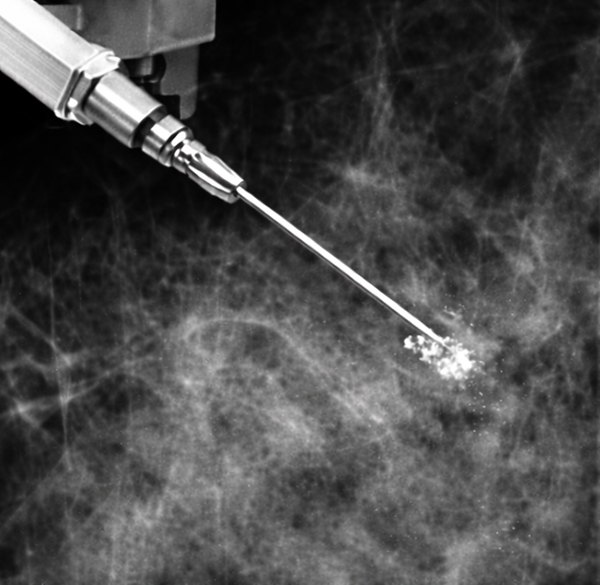

3D 맘모그래피(유방확대촬영기)를 활용해 병변의 위치를 확인한 뒤, 특수 바늘을 삽입해 미세석회화 주변 조직을 채취하여 양성·악성 여부를 판단하는 조직검사 방법입니다. 정밀한 병변 타겟팅으로 최소 침습적 조직 채취가 가능합니다.

01미세석회화 위치 확인

02검체 채취

03검체 확인

A스테레오탁틱 검사 시간은 약 30분~1시간 정도로,

유방촬영 영상을 기준으로 병변 위치를 계산한 뒤

국소마취 후 작은 절개를 통해 바늘로 조직을 채취합니다.